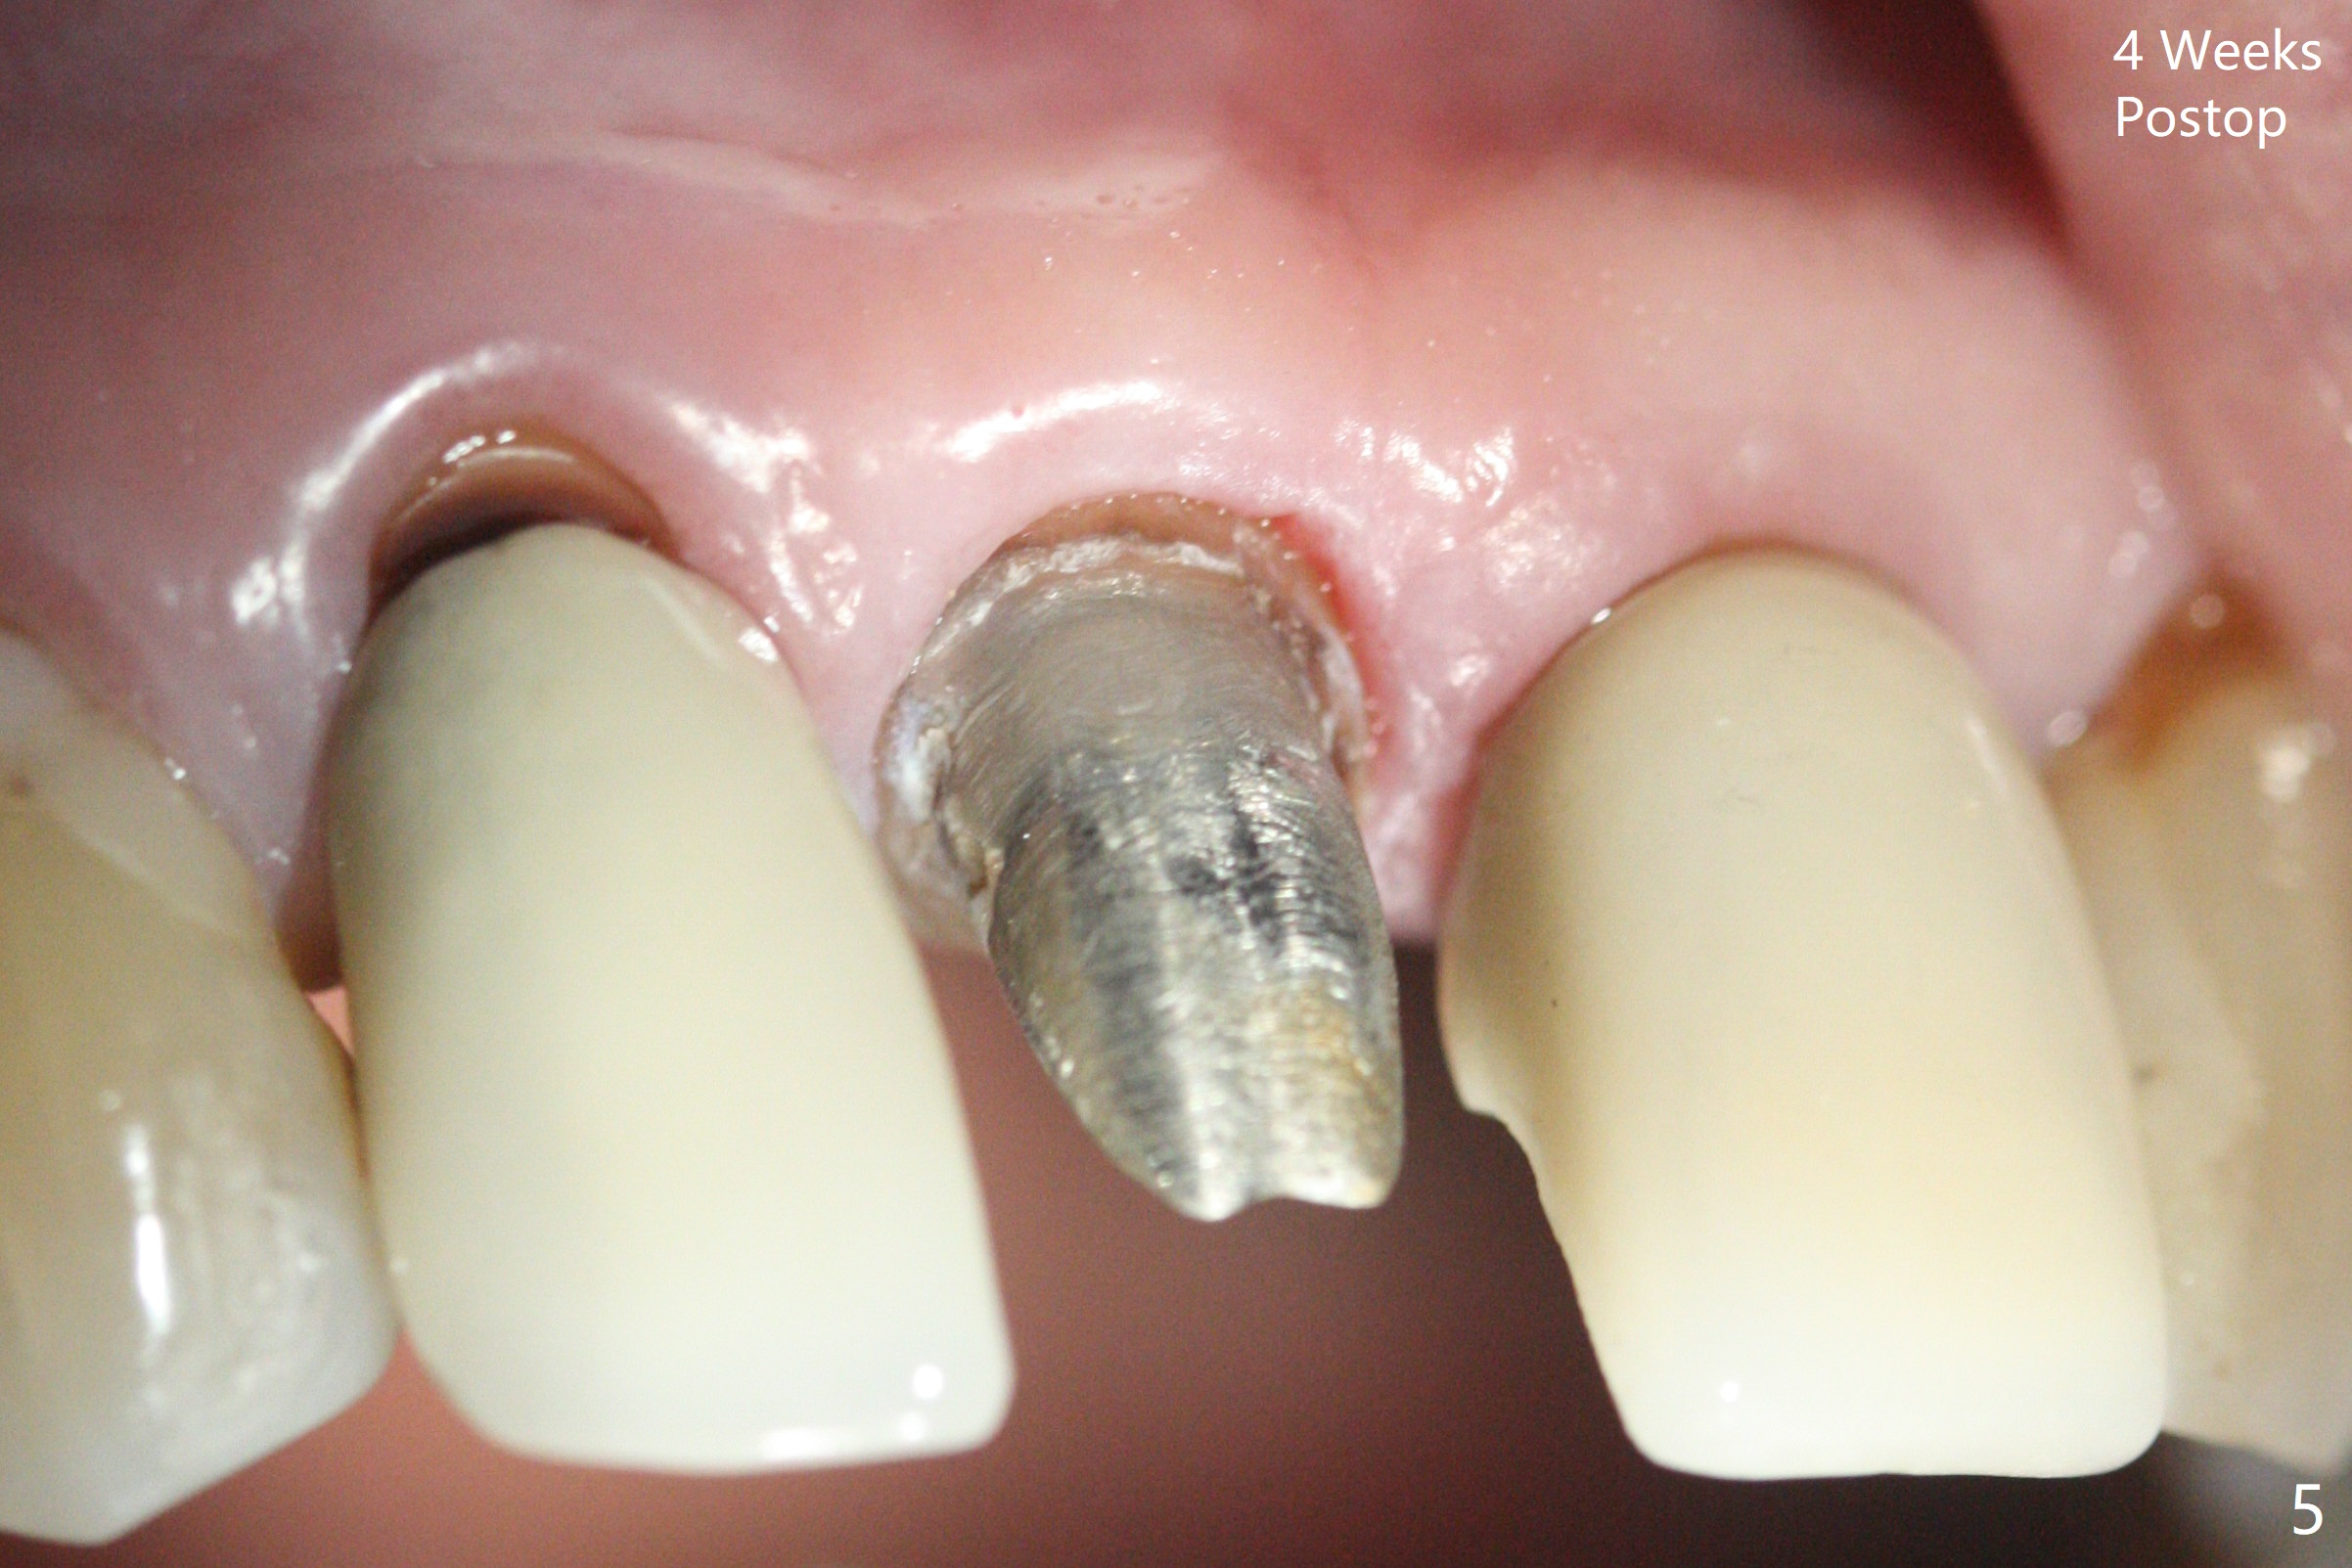

A 66-year-old man returns to clinic for #8 crown redo because of marginal leakage (Fig.1 *). After crown and caries removal, the tooth requires crown lengthening or basically non salvageable (Fig.2,3). For untold reasons, gingivectomy is performed with Waterlase without topical or local anesthesia. Hemostasis is excellent for impression, although there is wide spread of tissue debris from laser (Fig.4 >). The gingiva heals 4 weeks (Fig.5) and 6 weeks (Fig.6) postop.